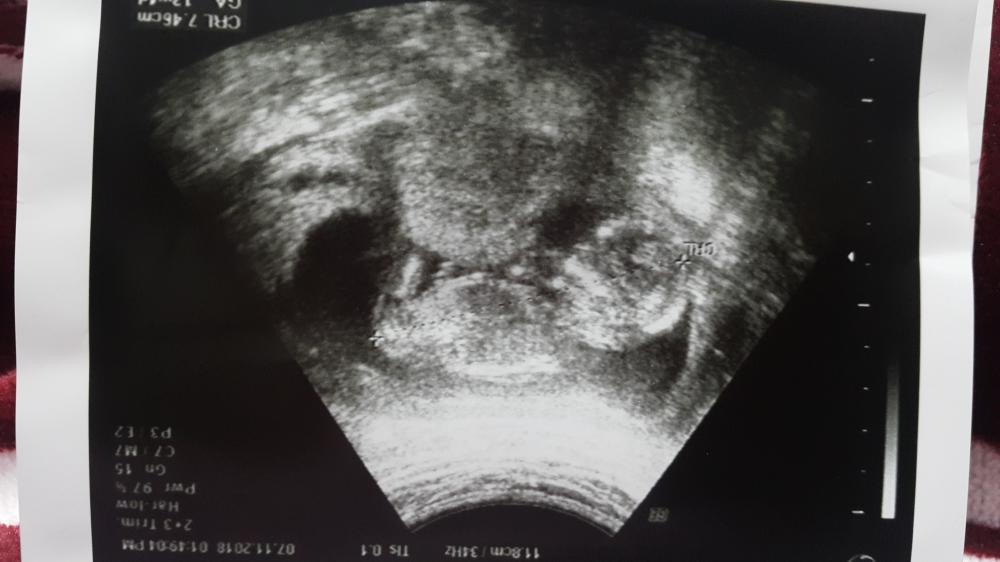

صورة بالسونار المهبلي هل هذا كيس الحمل ام تجمع دموي